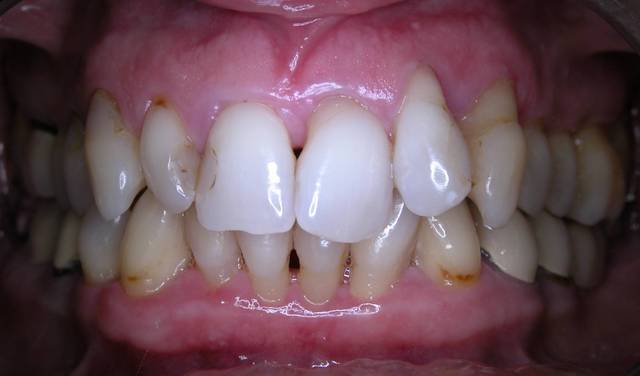

Voici le cas d'une patiente que j'ai traité pour une parodontite chronique.

Donc il s'agite d'une patient adressée par un confrère pour un avis paro avant un traitement ODf. La patiente a cinquante cinq ans. Elle fume des cigares, des problèmes d'hygiène. Je dignostique une parodntite chronique que j'ai traité en non chirurgical. La patiente est en observation avant d'entamer un traitement prothétique plutôt qu'ODF.

6 mois après: DSCN 0013

Le traitement ODF vu les pertes d'ancrage nécessitait une contention. La patiente était pressée, avec la prothèse on réalisait la contention et on pourra jouer sur l'esthétique. Bon là c'est son praticien, qui voit avec sa patiente. Pour moi ce qui est important c'est la contention, car il y a peu d'ancrage et gros troubles occlusaux.